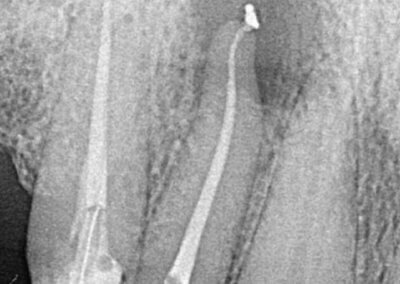

Endodonția este o ramură esențială a stomatologiei, axată pe diagnosticarea, prevenirea și tratamentul afecțiunilor pulpei dentare și a țesuturilor periapicale. Această specialitate joacă un rol crucial în salvarea dinților naturali, evitând extracțiile și menținând sănătatea orală pe termen lung. Prin tehnici avansate și echipamente de ultimă generație, endodonția asigură tratamente precise și eficiente, contribuind la redarea sănătății și funcționalității dinților într-un mod durabil și predictibil.

Utilizarea tehnicilor moderne asigură un tratament rapid, precis și confortabil pentru pacient.